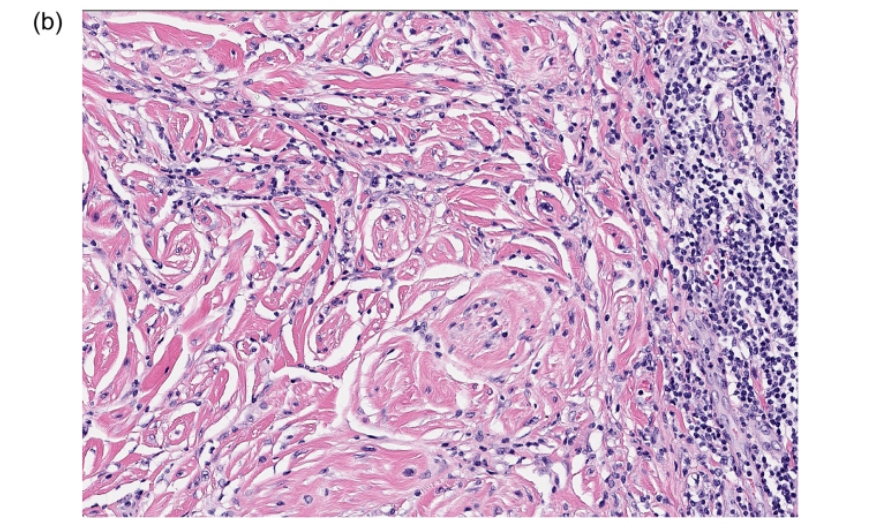

图2.促纤维组织增生型黑色素瘤,混合型。(A)真皮和皮下组织中可见相当大范围的无色素性、梭形细胞肿瘤;该肿瘤深部可见致密簇状肿瘤细胞;(B)富于细胞的区域高倍镜下可见非典型肿瘤细胞;此处未见间质的促纤维增生表现;(C)该肿瘤的另一部分,细胞密度较低,表现为纤维性间质内的单个肿瘤细胞和散在淋巴细胞。

混合型DM中,仅部分肿瘤有单纯型DM的特征,而其他部分则并无相关特征。具体如经典的表浅播散型、或肢端型黑色素瘤中可能会有部分促纤维组织增生型浸润性成分;还有一种情况是:其他方面均为单纯型DM,但有一处或数处继发性富于细胞的结节、或细胞丰富区域。

所谓的混合型DM也可用于细胞弥漫增多的梭形细胞型黑色素瘤伴少许间质促纤维组织的情况。其实这种情况更精确的名称应为细胞密度高的DM,但从实际工作的角度可以将其归为混合型DM。如果肿瘤细胞为致密束状、或簇状,但其间并无纤维性间质,则不能被归为单纯型DM。“单纯型”的命名应限于间质均一、富于细胞的单纯型黑色素瘤。

混合型DM中,细胞密度较高,一般细胞核非典型程度更高。常见多形性上皮样黑素细胞及核分裂。